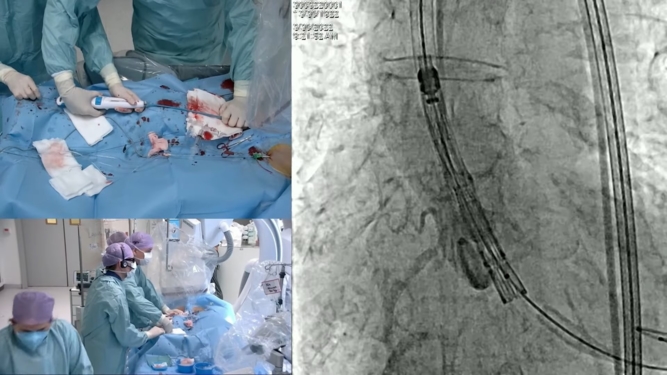

How to refine my TAVI procedure to ensure optimal long-term patient outcomes?